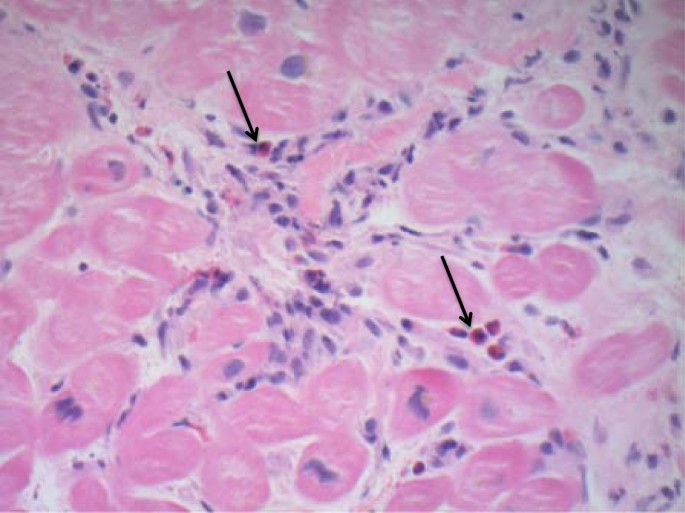

Межуточный миокардит: гистологические исследования